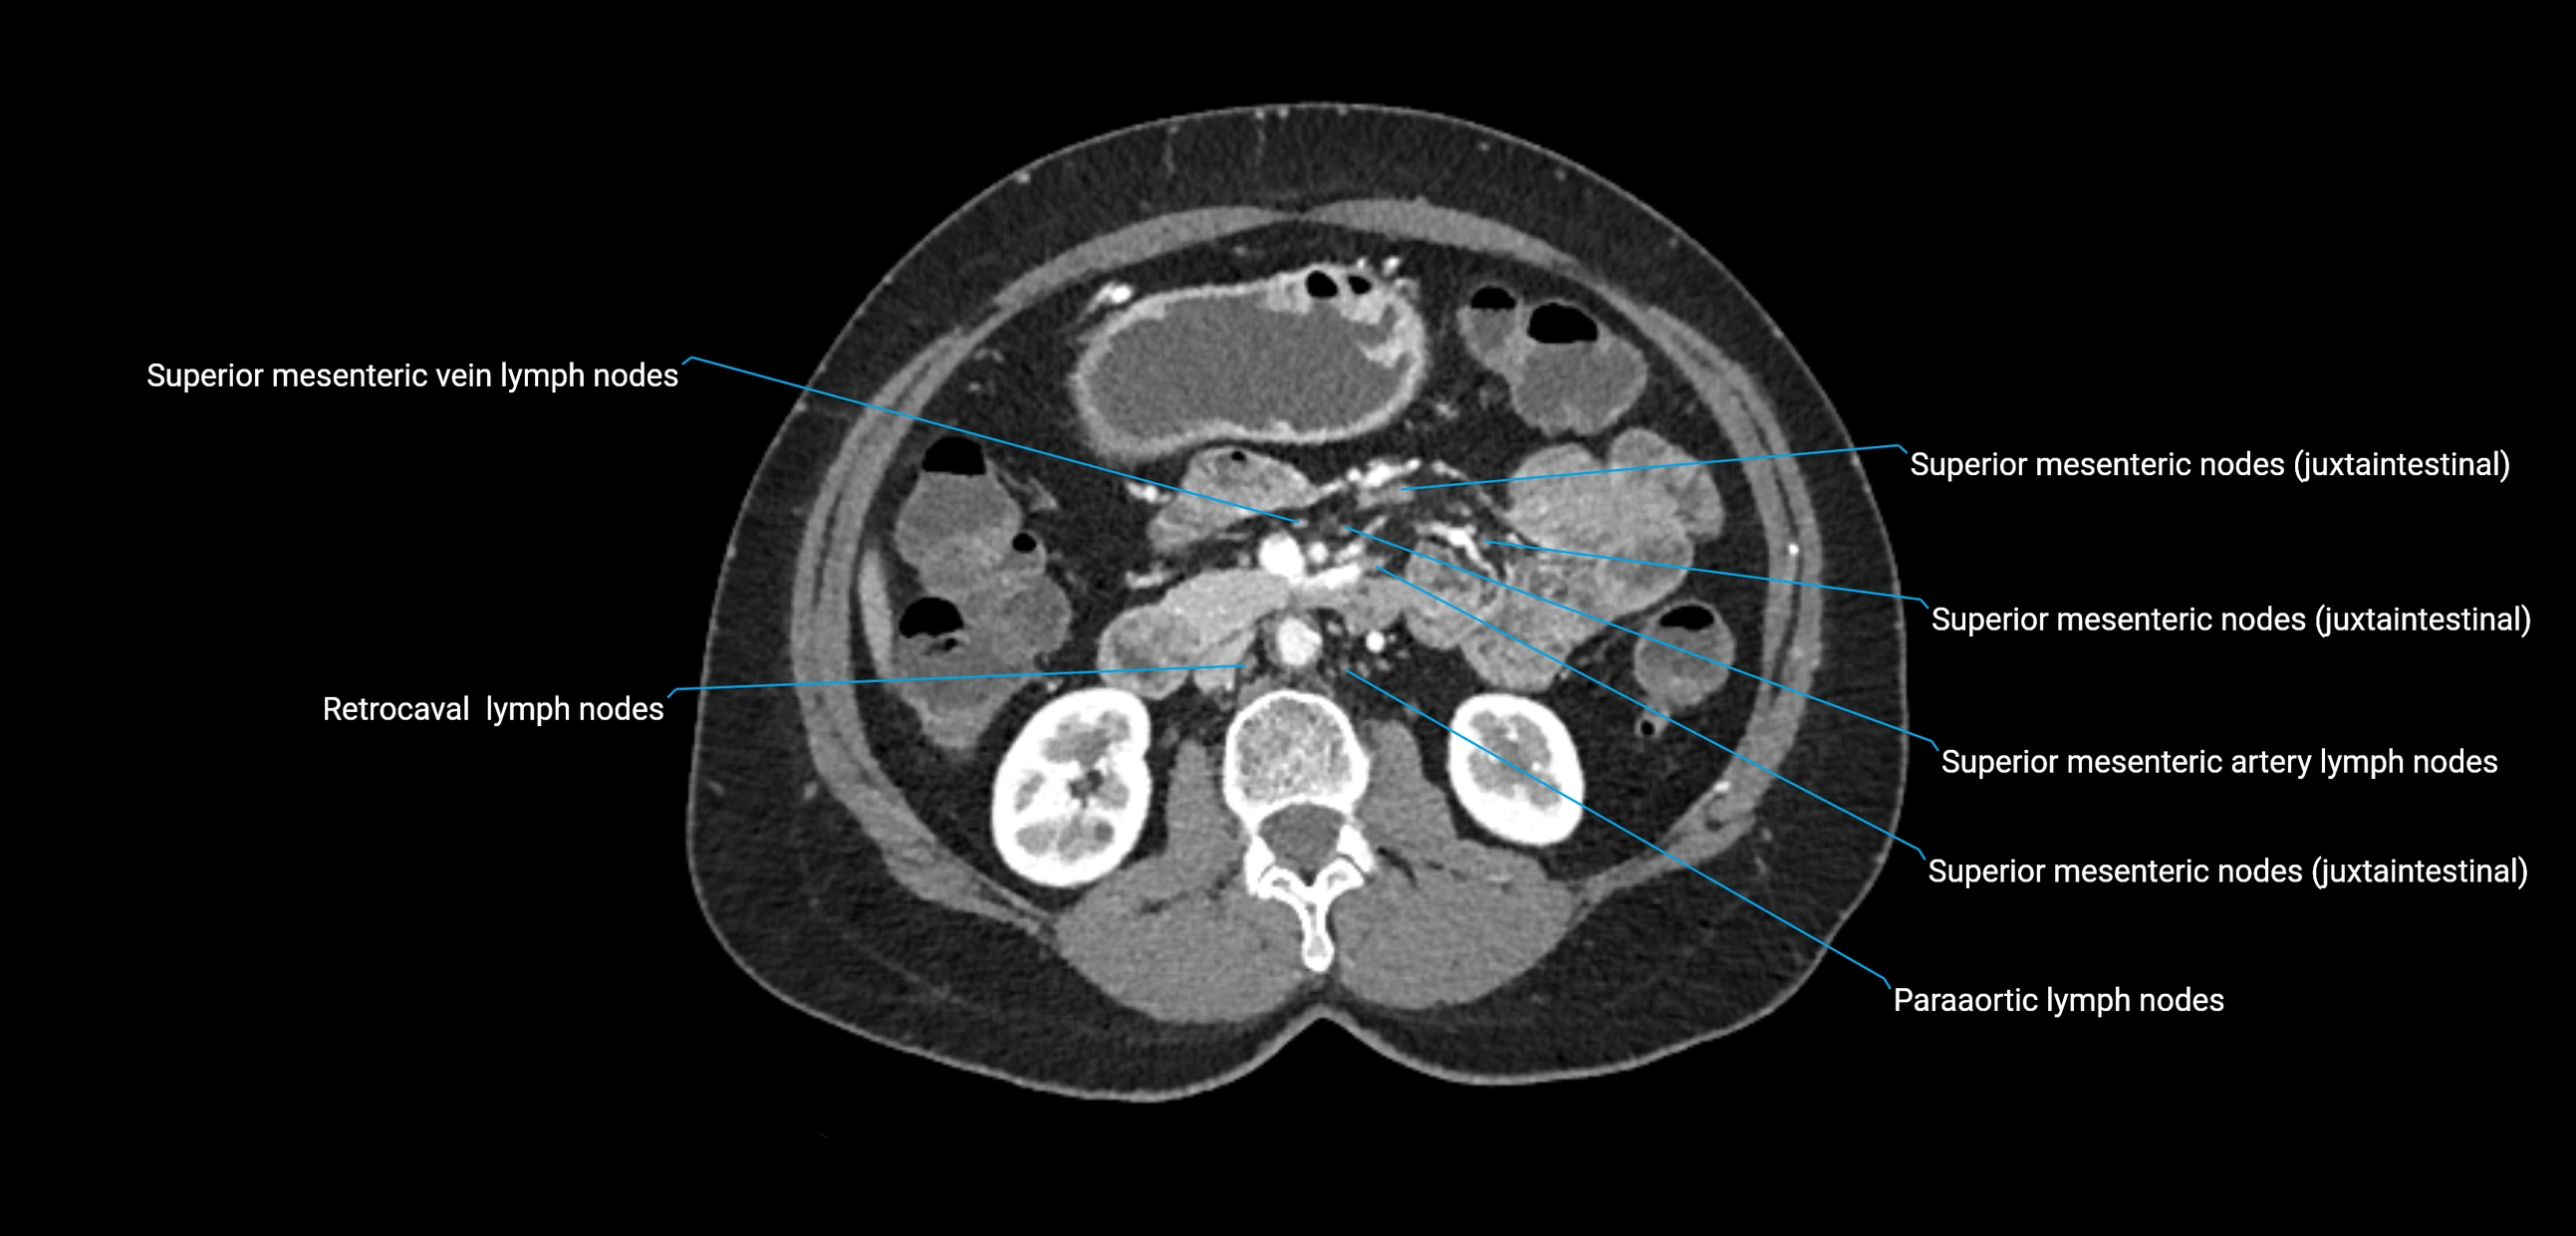

The lateral aortic lymph nodes (also called para-aortic lymph nodes) are a major group of retroperitoneal lymph nodes located along the abdominal aorta and its branches. They lie between the diaphragmatic crura superiorly and the bifurcation of the aorta at L4 inferiorly.

They are positioned on both sides of the abdominal aorta:

• Right lateral aortic nodes: adjacent to the inferior vena cava (IVC)

• Left lateral aortic nodes: lateral to the abdominal aorta

These nodes receive lymph from a wide range of abdominal and pelvic structures. Specifically, they drain lymph from the kidneys, suprarenal glands, gonads (testes/ovaries), uterus, uterine tubes, and pelvic organs, before converging into the lumbar lymphatic trunks, which terminate in the cisterna chyli → thoracic duct.

CT Appearance

CT Pre-Contrast:

• Nodes appear as soft-tissue density nodules adjacent to the aorta and IVC

CT Post-Contrast:

• Normal nodes enhance homogeneously

• Malignant nodes may show heterogeneous enhancement, central necrosis, or conglomerate formation

• Size >1 cm short axis is suspicious, though morphology and distribution are equally important